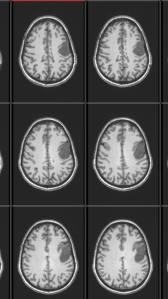

She has a 4.3 x 2.9 x 3.3 cm dural based mass overlaying the left frontal lobe, superior to the operculum. It is (likely-95%) a benign neoplasm. The Meningioma has grown between her meninges and has encroached on the brain. It’s likely been there growing for 20-30 years. She has increased bone mass over the site due to the tumor, which is one way they can tell it’s been there a long time. She has had very little symptoms until recently.

The pic is from an fMRI, so it’s not quite as clear, but you’ll get the picture. I’ll see about posting a clear pic of her other MRI later.